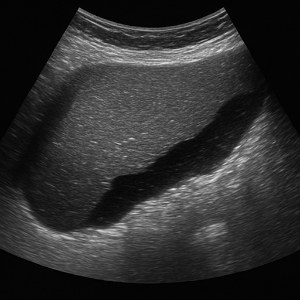

신장은 결석, 수신증(소변이 막혀 고여서 생긴 변화), 낭종, 종양 등의 상태를 초음파로 볼 수 있어요. 부신은 위치가 작고 깊지만, 우연종 같은 병변이 의심될 때 관찰할 수 있답니다.

신장 결석, 신부전, 낭종

- 신장 결석

콩팥에 생긴 작은 돌들은 초음파에서 반짝이며 그림자를 동반해 쉽게 보일 수 있어요. - 신부전 (수신증 등)

소변이 막혀서 신장이 붓는 상태를 ‘수신증’이라고 하는데요, 초음파로 신장의 부종이나 이상을 확인할 수 있어요. - 신장 낭종이나 종양

주머니처럼 생긴 낭종이나 덩어리가 있으면 초음파로 확인 가능해요.

소변에 피가 섞여 나오면 신장이나 요로에 문제가 있을 수 있어요. 혈뇨의 원인이 될 수 있는 신장 결석, 낭종, 종양, 수신증(소변이 막혀 신장이 부어오르는 상태) 등을 복부초음파로 확인할 수 있어요.